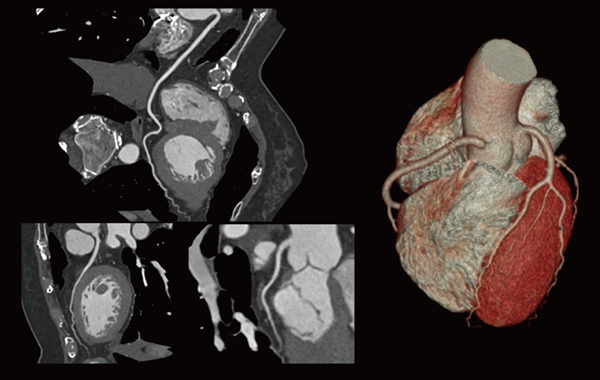

[CT 5300の臨床画像]

低被ばく高画質心臓CT画像

(Precise Image,CTDIvol 22mGy)

なお,CT 5300はBrilliance iCTよりも時間分解能が低いため,中川事務長は当初,心臓CTの画質に若干の懸念があったというが,「CT 5300は心臓の再構成プロトコールが優れているため,比較的良好な画像が得られます。心拍にブレのある症例などでは,心臓専用AIモーション抑制の『Precise Cardiac』を使用することで,ブレの少ない画像が得られています」と評価している。